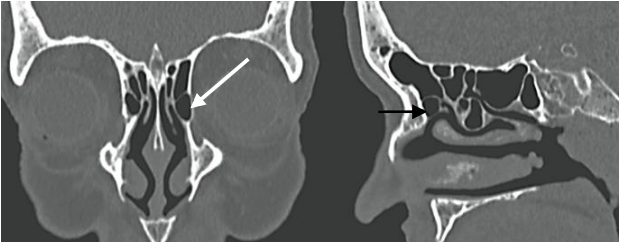

A estrutura apontada pela seta corresponde a:

A imagem a seguir corresponde mais provavelmente a: